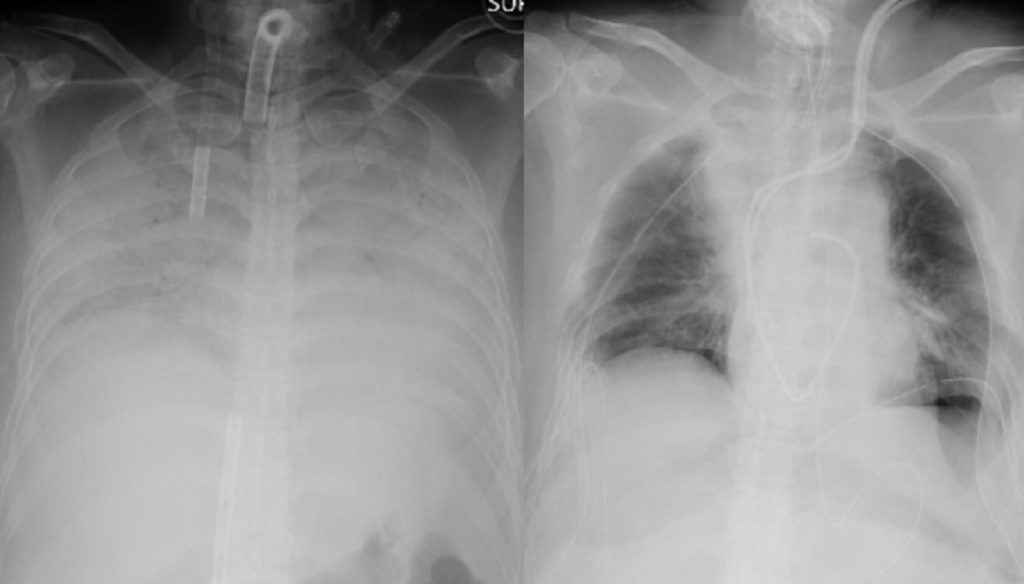

জাপানের কোয়োটা ইউনিভার্সিটি হাসপাতাল কর্তৃপক্ষ জানায়, সম্প্রতি ওই নারীর শরীরে করোনা সংক্রমণের ফলে তার ফুসফুস দুটি মারাত্মকভাবে ক্ষতিগ্রস্ত হয়। এতে তার বেঁচে থাকার সম্ভাবনা ক্ষীণ হয়ে পড়ে। পরে এই হাসপাতালের চিকিৎসকরা সিদ্ধান্ত নিয়ে ওই নারীর স্বামী ও ছেলের সুস্থ ফুসফুস তার দেহে প্রতিস্থাপন করতে সফল হন। ৩০ জন বিশেষজ্ঞ চিকিৎসকের জটিল এই অস্ত্রোপচার করতে সময় লেগেছে প্রায় ১১ ঘণ্টা।

করোনার ফলে ওই নারীর নিউমোনিয়া হয়ে গিয়েছিল। তবে সফল অপারেশনের পর ড. হিরোশি এখন আশা করছেন দ্রুত সুস্থ হয়ে উঠবেন ওই নারী।